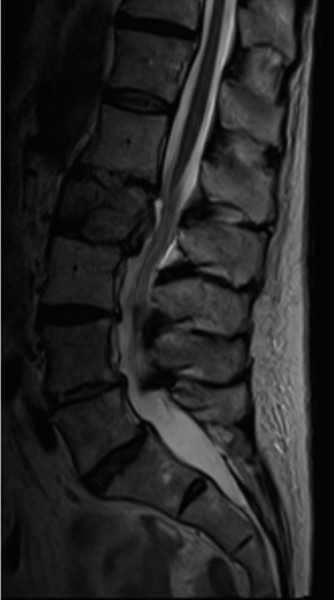

To definitively assess the integrity of the soft tissue stabilizers and the neural elements, a Magnetic Resonance Imaging (MRI) scan without contrast was performed. Historically, textbooks propagated the "50-50-25 rule," suggesting that a burst fracture was inherently unstable if it exhibited >50% canal compromise, >50% loss of vertebral body height, or >25 degrees of kyphosis. Modern spine trauma surgery has largely debunked this rigid radiographic dogma. We now understand that these bony metrics alone do not dictate mechanical instability. The true arbiter of stability is the Posterior Ligamentous Complex (PLC).

The MRI, particularly the Short Tau Inversion Recovery (STIR) and T2-weighted sagittal sequences, provided the definitive diagnosis. The images demonstrated profound hyperintensity and discontinuity of the ligamentum flavum, the interspinous ligaments, and the supraspinous ligaments at the T12-L1 level. The facet joint capsules were also disrupted, indicated by fluid within the joints. This complete failure of the PLC means the posterior tension band is gone. Regardless of the bony parameters, this spine cannot resist physiological flexion loads. If treated non-operatively, this injury will inevitably lead to progressive kyphosis, delayed neurological deficit, and intractable pain.